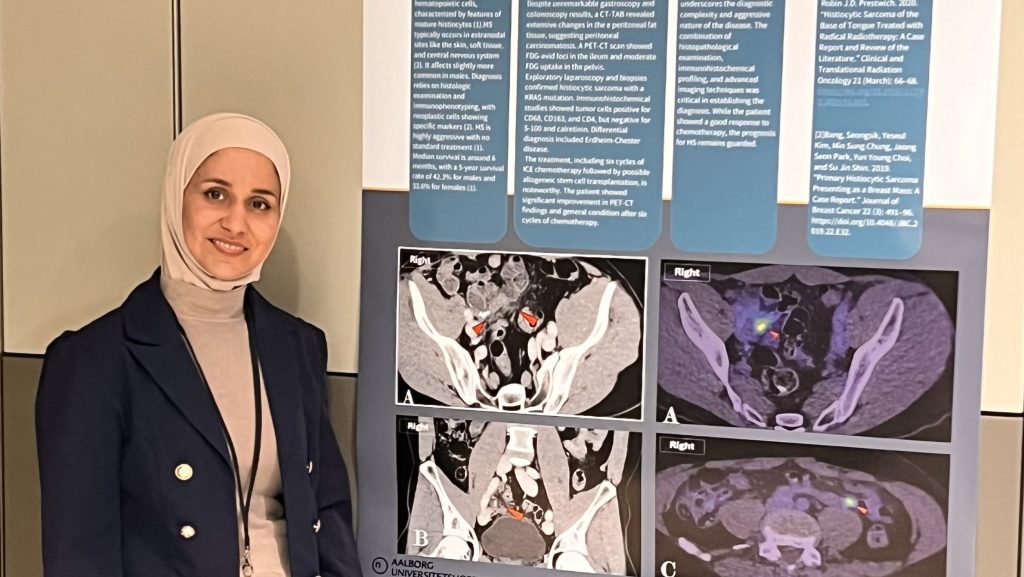

Ny CASE RAPPORT

Vores dygtige kollegaer fra Radiologisk afdeling på Aalborg Universitetshospital Louise… Læs mere